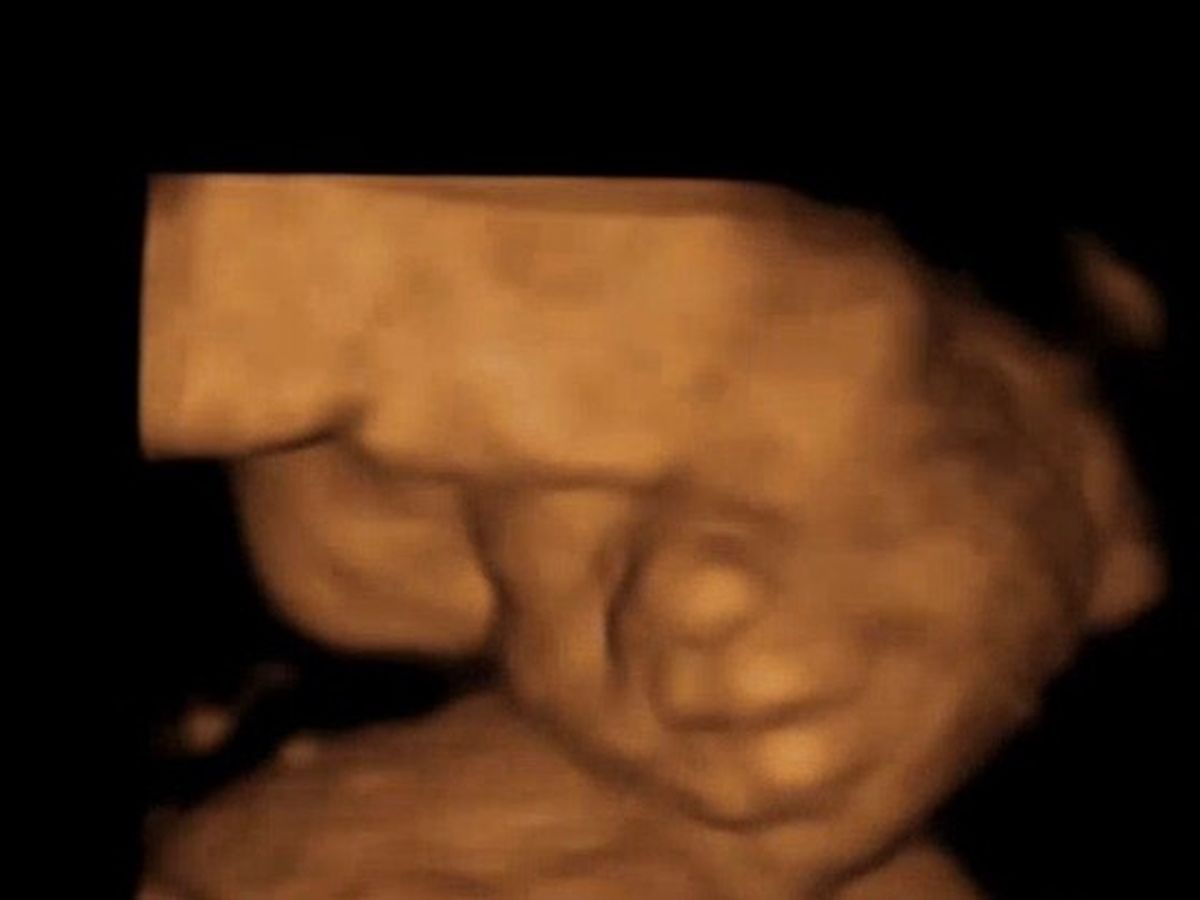

In July of 2025 our sweet cousin found out she was expecting her first child. Little did she know at her first ultrasound she would be told very heart breaking news. The baby has a condition where the skull fails to develop leaving the brain unprotected. After meeting with her OB and a high risk specialist in Birmingham she was given no hope. She ended up doing her own research on this condition and has since found a specialist in New Jersey that is willing to go above and beyond to give this baby every chance at life possible. With that comes a lot of expenses including travel to meet with these doctors. As we all know times are hard right now for everyone but if you feel in your heart to help this precious family, we all greatly appreciate. More than anything they need your prayers that everything works out and a miracle happens!